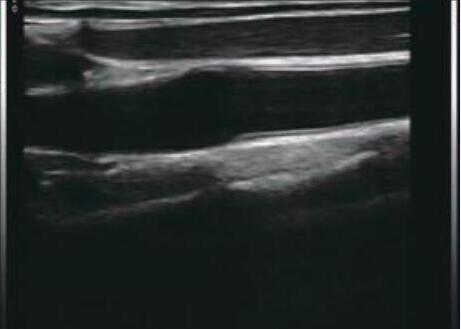

Pocket Ultrasound Scanner Portable Color Doppler Application for MSK Breast Thyroid

This ultrasonic probe was launched in 2018, the probe body has 3 activation buttons, scanning frequency is 7.5-10mhz,

192 elements. Color Doppler wireless linear probe, can provide rapid high-definition ultrasound images for anesthesiologists,

physiotherapists, etc.

Images

Color Doppler Portable Pocket Ultrasound Scanner Application For MSK Breast Thyroid Images |